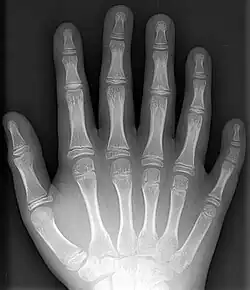

Polydaktyli er en misdannelse som indebærer, at man har flere end fem fingre på hver hånd eller flere end 5 tæer på hver fod. Begrebet stammer fra græsk, poly, mange og daktylos, finger. Det er arveligt, men optræder ofte uregelmæssigt, eftersom arveanlægget ikke altid manifesterer sig. Selvom tilstanden ikke er farlig, får de fleste mennesker i Vesten fjernet ekstra udvækster kirurgisk.

En ekstra finger vil kun sjældent være en komplet og velfungerende finger; normalt består den blot af muskelvæv og til tider også et stykke knogle uden forbindelse med de øvrige knogler. Normalt er den ekstra finger en lillefinger på siden af hånden, kun sjældent optræder den på tommelsiden af hånden, og i meget sjældne tilfælde findes den mellem de andre fingre.